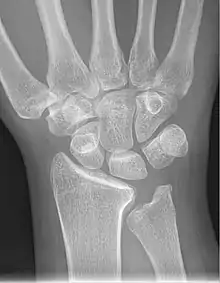

Radiographic classification

First described by David Lichtman et al. in 1977.[7] The purpose of this classification system is to guide treatment and to enable comparison of clinical outcomes.

1. Stage I Normal radiograph (possible lunate fracture).

2. Stage II Sclerosis of the lunate without collapse. (Portions of the lunate begin to deteriorate. This shows as a white blemish on x-rays.)

3. Stage IIIA Lunate collapse and fragmentation, in addition to proximal migration of the capitate.

4. Stage IIIB Lunate collapse and fragmentation, in addition to proximal migration of the capitate. In addition there is fixed flexion deformity of the scaphoid.

5. Stage IV Changes up to and including fragmentation, with radiocarpal and midcarpal arthritic changes.